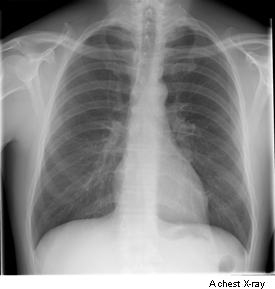

An x-ray is a test that uses small amounts of radiation to take pictures of the inside of your body. They are a good way to look at bones and they can show changes caused by cancer or other medical conditions. X-rays can also show changes in other organs, such as the lungs.

chest x-rays to show fluid, signs of infection, an enlarged heart or tumours in the chest such as lung cancer

You usually have a chest x-ray standing up against the x-ray machine. If you can’t stand you can have it sitting or lying on the x-ray couch. For x-rays of other areas of the body the best position is usually lying down on the x-ray couch.